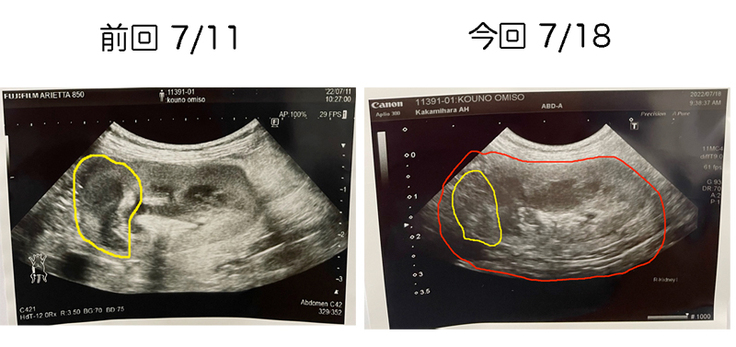

前回のエコーでは、腫瘍が少し小さくなっていました。

今回のエコーでも、腫瘍が小さくなっており、なんと今まで映らなかった腎臓の形も見られるにまで良くなっていました。